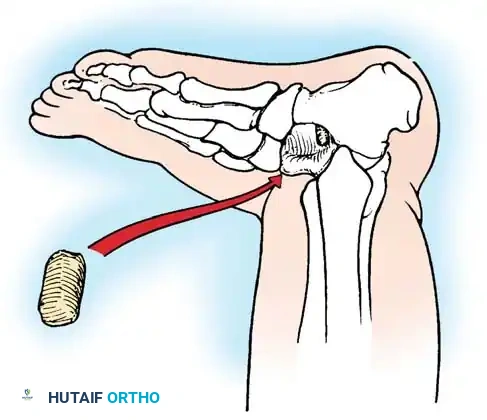

For infants and young children, a single-stage minimally invasive or limited-open approach has gained traction. Kodros and Dias described a highly effective technique utilizing a threaded Kirschner wire (K-wire) as a "joystick" to manipulate the vertical talus into an anatomic position.

Technique Overview:

1. A threaded K-wire is introduced axially into the vertical talus from a posterior approach.

2. The wire is utilized as a joystick to lever the talus out of equinus and medial deviation, elevating the talar head.

3. Simultaneously, the forefoot is plantarflexed and inverted to reduce the navicular onto the talar head.

4. Once anatomic reduction is confirmed fluoroscopically, the K-wire is advanced across the talonavicular joint to secure the reduction. Additional wires may be placed across the subtalar joint.